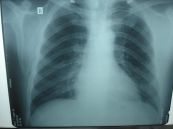

X-quang ngực được thực hiện để giúp tìm ra nguyên nhân của các triệu chứng phổ biến như ho, khó thở hoặc đau ngực, các vấn đề về phổi như viêm phổi, ung thư phổi, bệnh phổi tắc nghẽn mạn tính (COPD),... Dưới đây là một số thông tin chi tiết về thủ thuật, mời các bạn tham khảo!